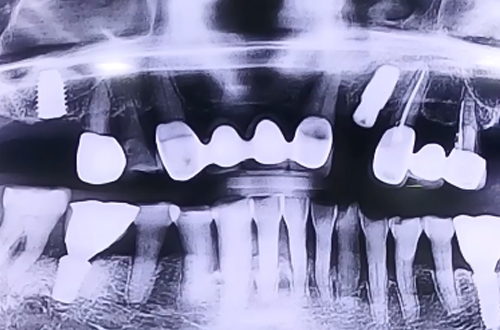

AFTER

오른쪽 위 가장 안쪽에 있는 어금니에 임플란트를 진행한 환자분이십니다.

상악동에 임플란트가 빠지지 않도록 뼈 없는 공간에 뼈를 올려주면서 상악동거상술과 뼈이식을 이용하여 임플란트 치료를 진행해 드렸습니다.

뼈이식을 많이 하게 되면 뼈이식한 뼈들이 단단하게 굳는 6개월 정도의 기간을 충분히 기다려준 뒤 보철이 완성되면 다음 진료일지로 찾아뵙도록 하겠습니다. ^^!